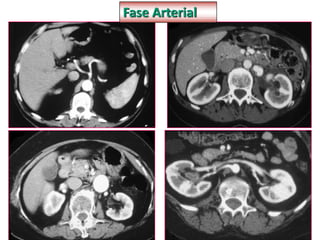

Fase Arterial

§ Hipervascular

§ Cortes de 1mm

§ Débito de 2ml/s injetora

§ Dose 2ml/kg

§ Delay 20-40 segundos

§ Avaliar lesões hipervasculares tumorais

§ Avaliação vascular

§ Avaliação de fugas de produto de contraste/

sangramento